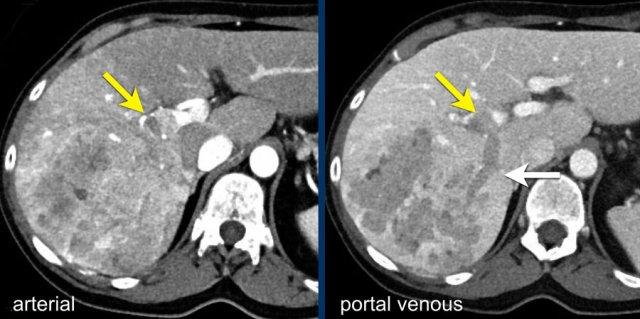

Tất cả các hình ảnh này đều của một bệnh nhân không có xơ gan, do đó chúng ta không thể áp dụng hệ thống LI-RADS.

Có nhiều tổn thương không đồng nhất với ngấm thuốc ngoại vi nhẹ ở thì động mạch.

Một số tổn thương giảm tỷ trọng nhẹ so với nhu mô gan lân cận ở thì cửa, và các tổn thương lớn hơn có trung tâm hoại tử.

Tính đa ổ và kiểu ngấm thuốc dạng bia không điển hình cho HCC và gợi ý bệnh lý di căn.

Bệnh nhân này được chẩn đoán u thần kinh nội tiết với di căn gan.

Các hình ảnh này thuộc về một bệnh nhân có gan nhiễm mỡ.

Mặc dù một số bệnh nhân này có nguy cơ phát triển HCC cao hơn một chút, chúng ta vẫn không thể áp dụng hệ thống LI-RADS.

Có nhiều tổn thương ngấm thuốc mạnh ở cả thì động mạch và thì tĩnh mạch cửa.

Đây là một ví dụ khác về di căn tăng sinh mạch.

Bệnh nhân này đã được biết là có u thần kinh nội tiết của tụy.